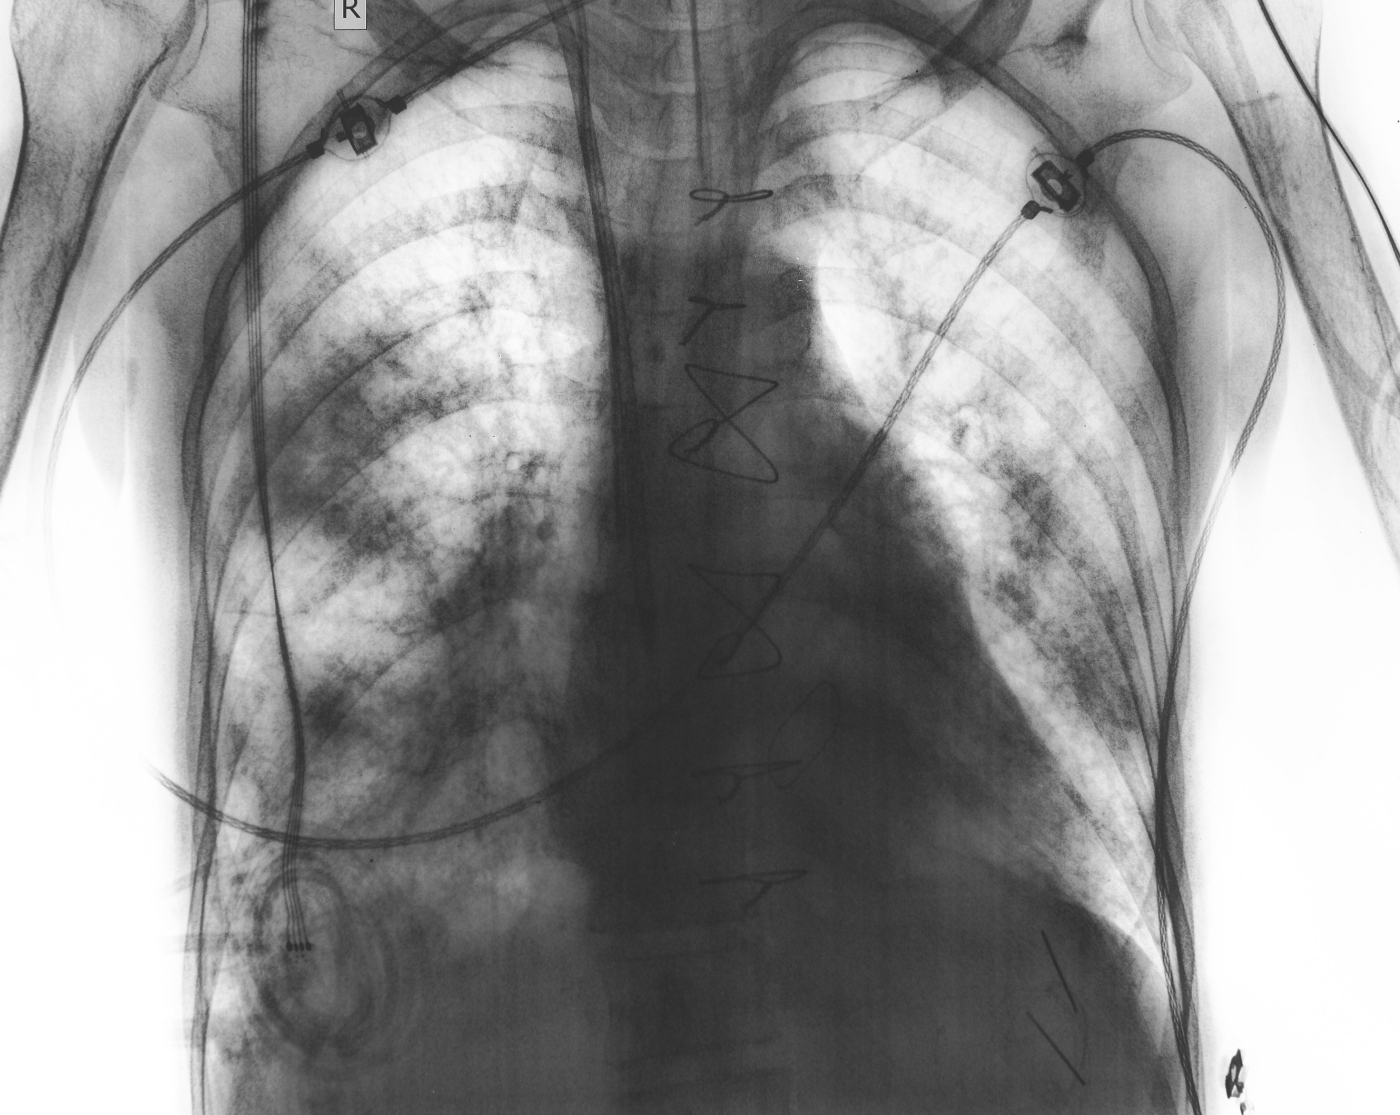

2. Paru-paru mengempis (pneumothorax)

COPD boleh merosakkan tisu paru-paru. Jika terdapat udara bocor keluar dan masuk ke dalam ruang antara paru-paru dan dada, paru-paru akan mengempis seperti belon yang dibuang angin. Simptom yang dialami adalah nafas pendek secara tiba-tiba, sakit atau dada terasa sempit dan batuk.

Rawatannya mungkin hanya memberikan oksigen atau prosedur memasukkan tiub di dada untuk mengeluarkan angin yang bocor.